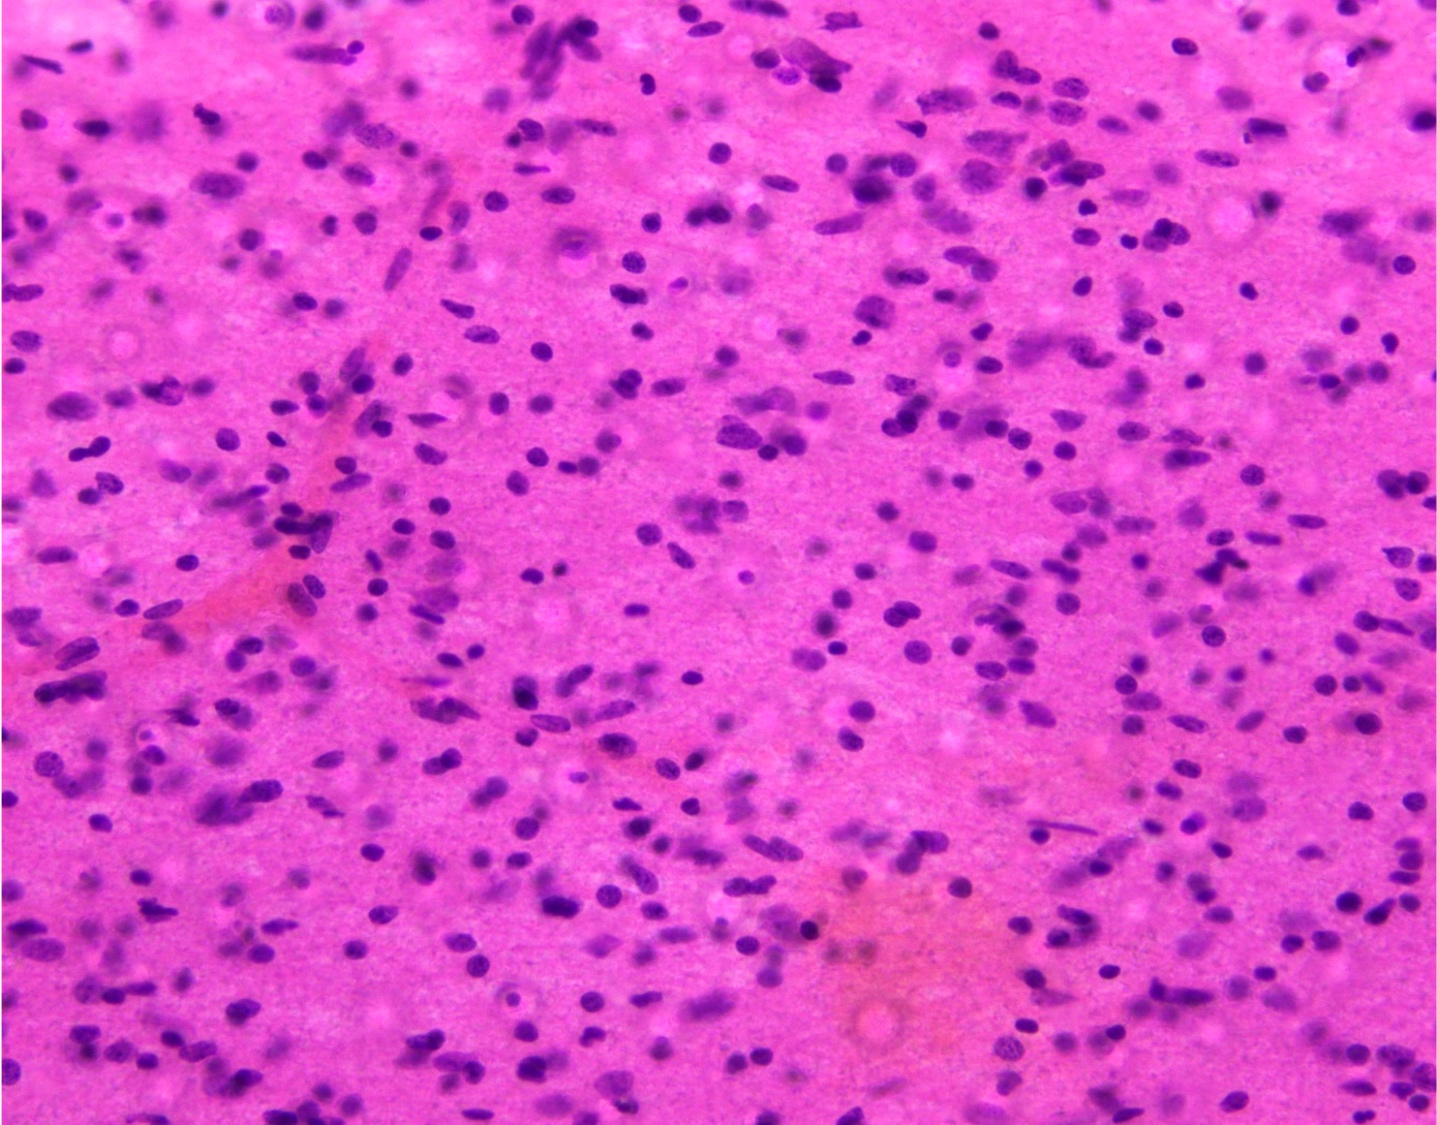

Microscopic (histologic) description

- Closely packed cells with small, round, monotonous nuclei (slightly larger than a normal oligodendrocyte)

- Perinuclear clearing (fried egg appearance)

- Formalin fixation artifact

- Will not be seen on frozen sections or smear preparations

- Network of thin walled, branching blood vessels (chicken wire vasculature)

- Microcalcifications (calcospherites) are characteristic

- Presence of perineural, perivascular or subpial aggregates of tumor cells (secondary structures of Scherer)

- Occasional mitoses and moderate nuclear atypia are still consistent with grade 2 designation (J Neuropathol Exp Neurol 2001;60:248)

- Not uncommon to find well differentiated / fibrillary astrocytic morphology (Acta Neuropathol 1984;64:265)

Microscopic (histologic) images

Contributed by Jared T. Ahrendsen, M.D., Ph.D. and John DeWitt, M.D., Ph.D.